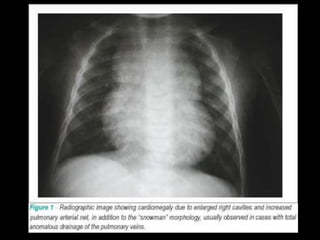

Diagnosis

Chest X-Ray:

• Snowman or figure of 8 appearance

• Cardiomegaly

• Plethoric lung field